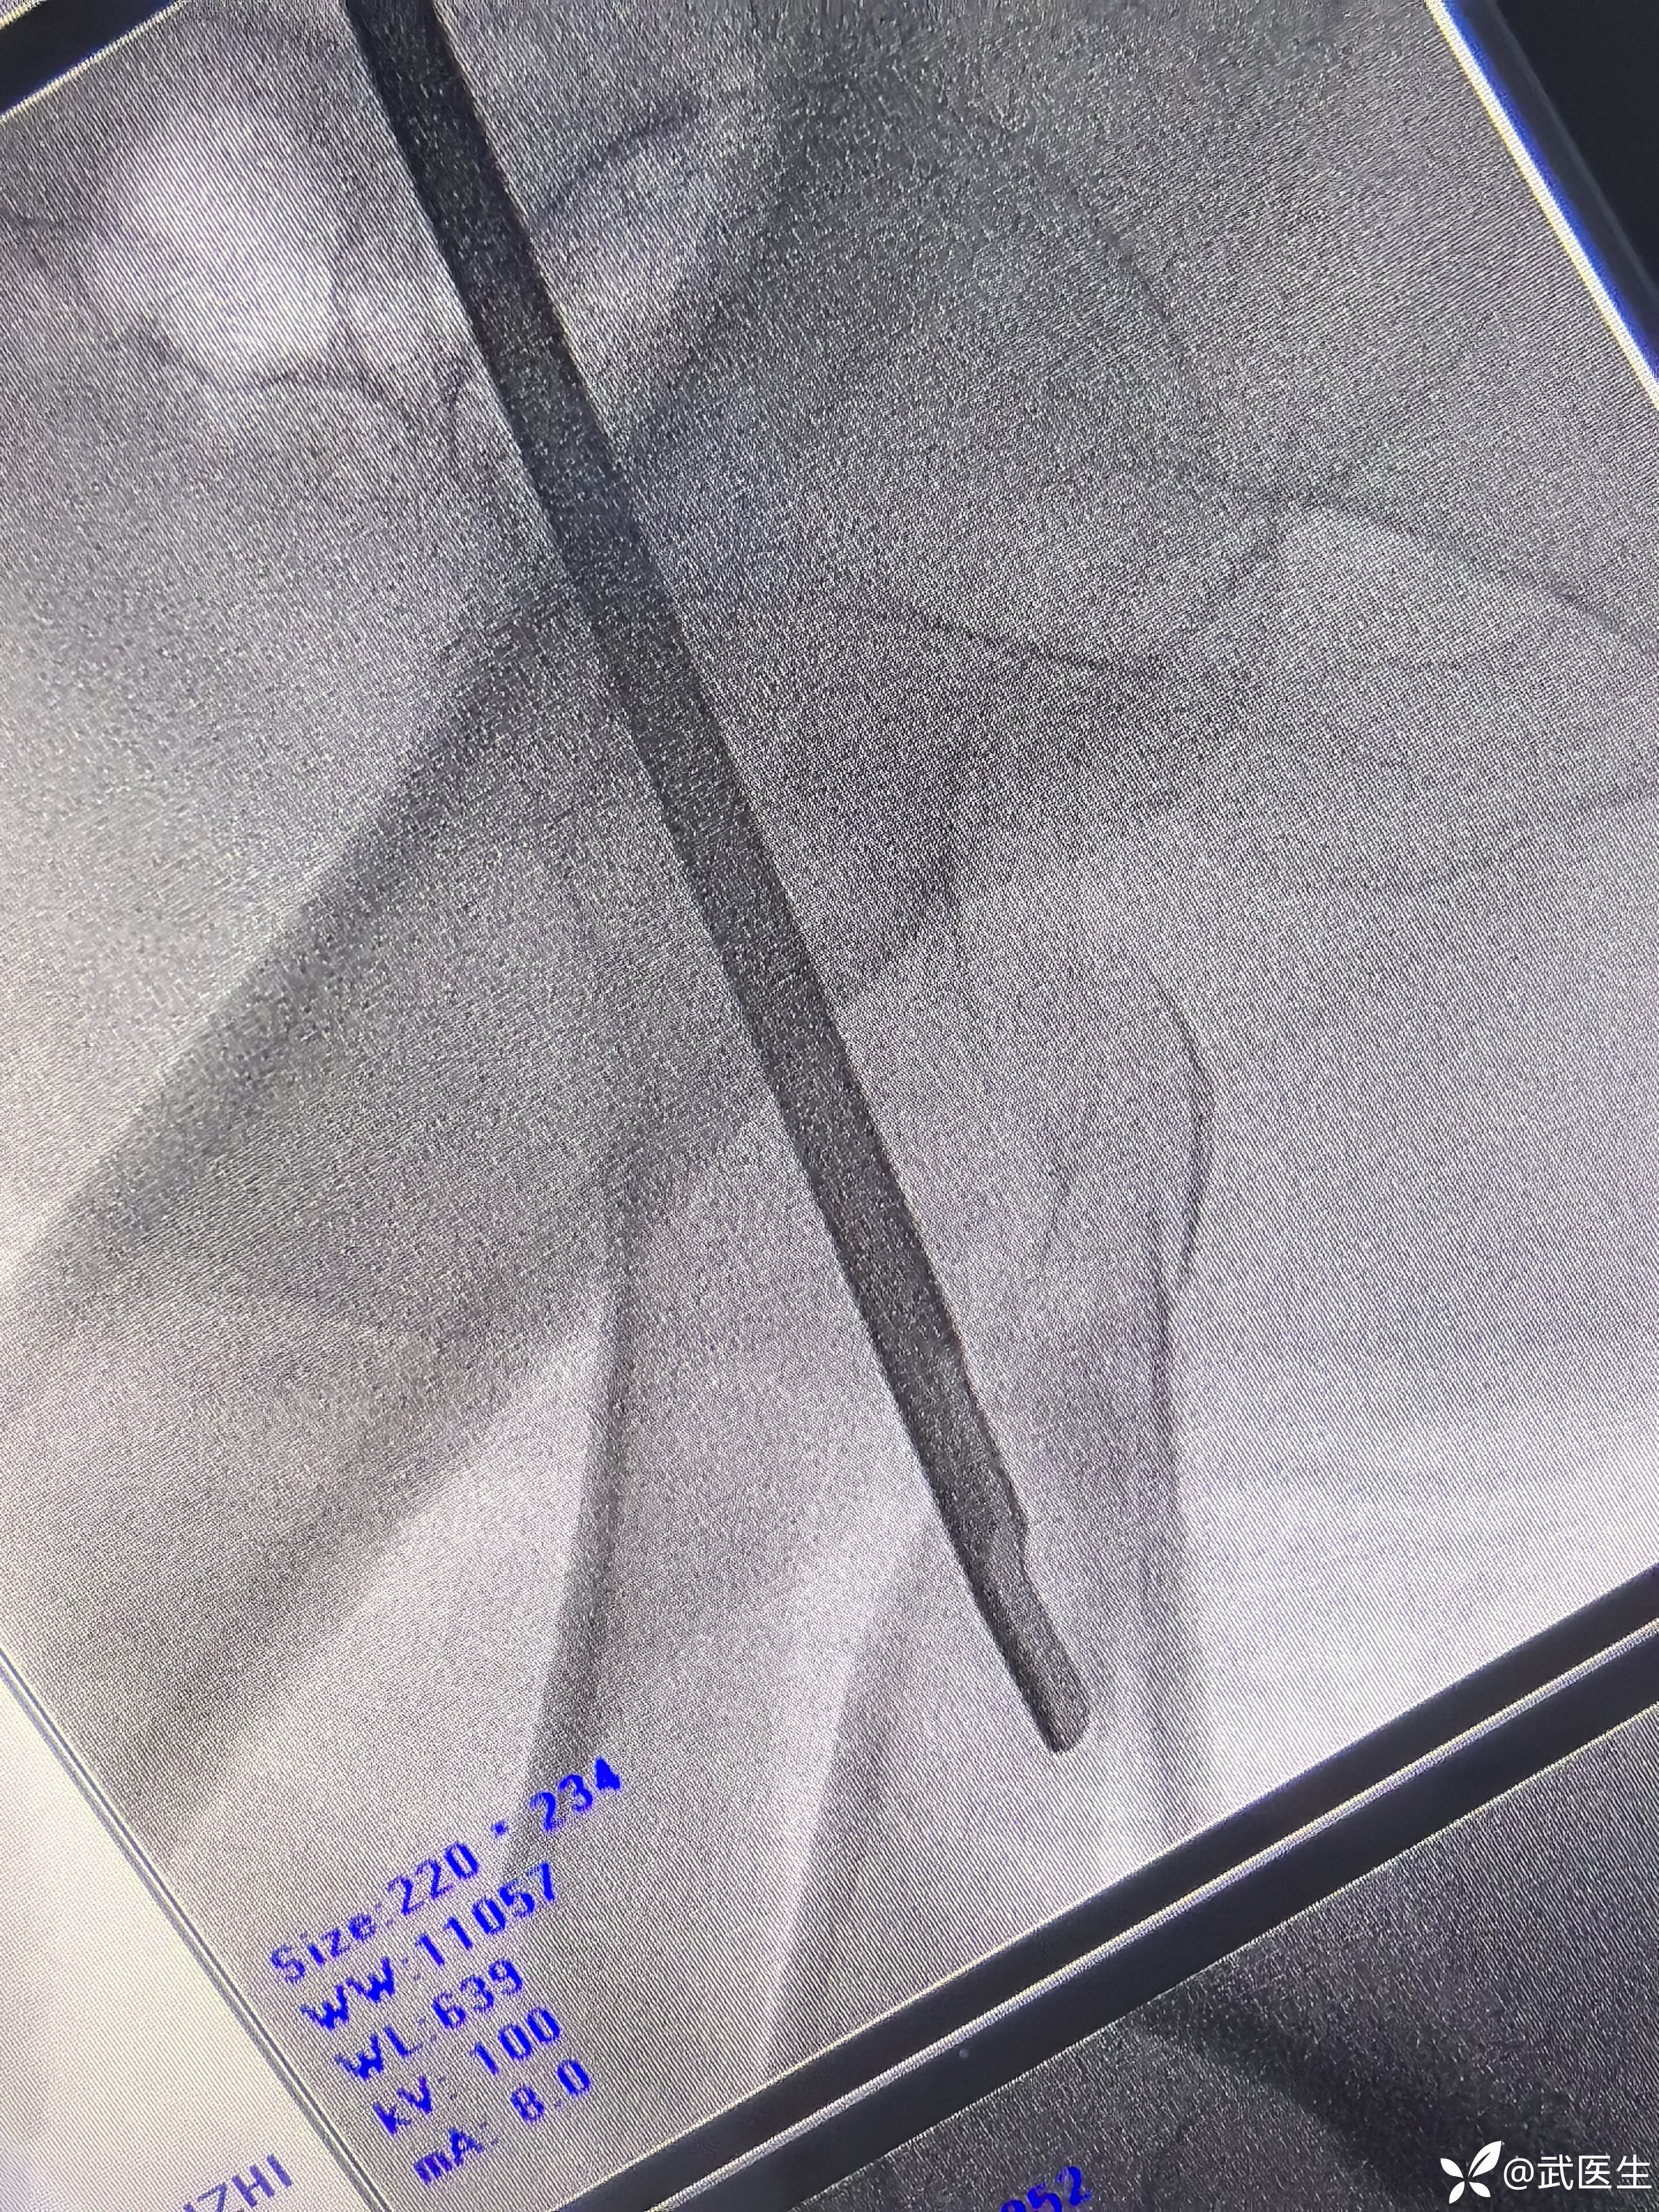

打头颈导针

正位,头颈导针居中偏下,可以

轴位,居中略偏前,能接受

这个轴位,又好了,不错,应该是投照角度问题,本来就好。